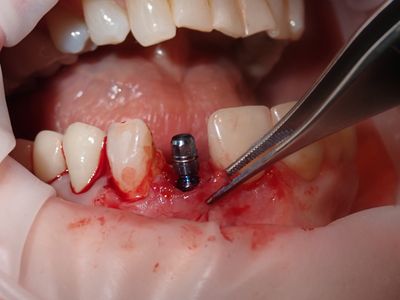

Atraumatic exo, loss of labial plate mid root about 2-3mm, CEJ and apical bone intact, region of thinner Labial-palatal bone, flapped site. osteotomy underprepared, implant placed with excellent stability. Buccal and socket grafted with 90/10 mix of mineralized cortical/xenograft followed by collagen membrane outside of socket on buccal, implant loaded with temporary crown out of centric and protrusive occlusion